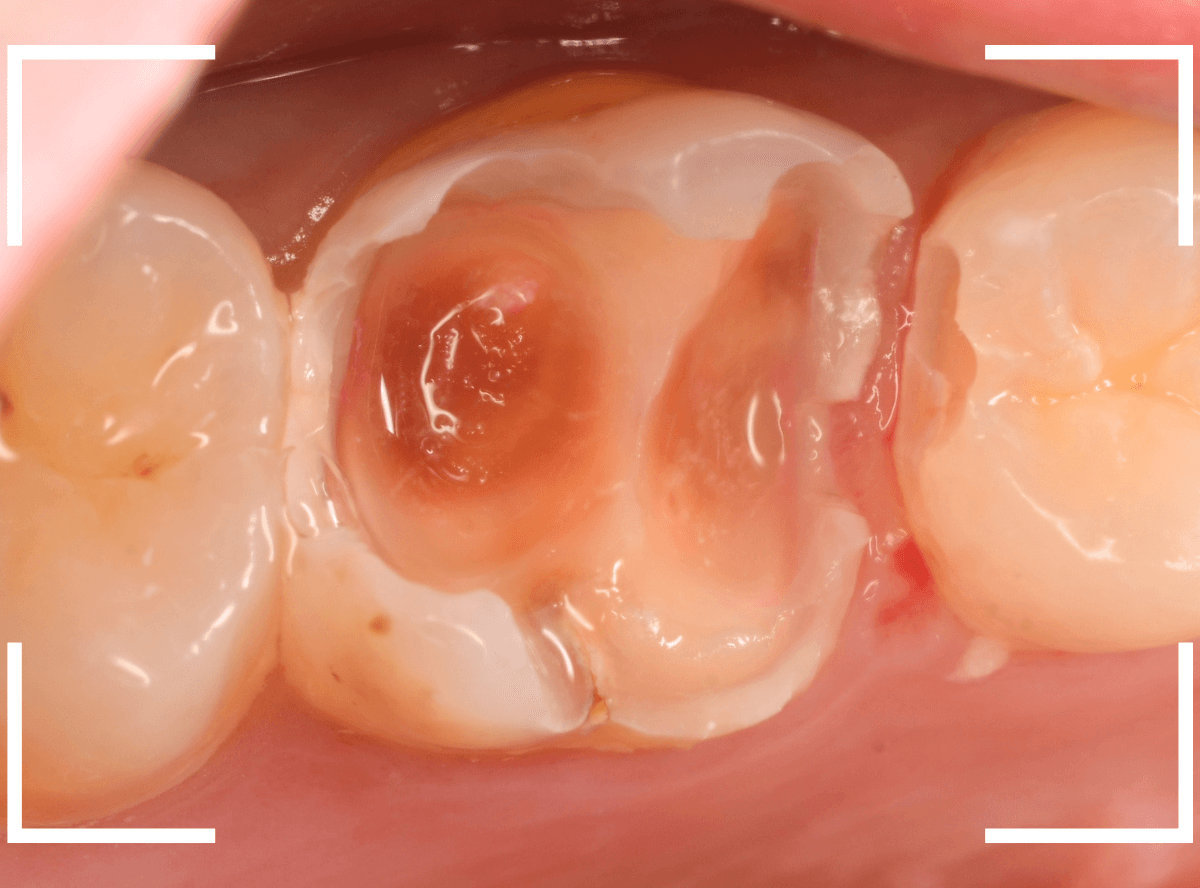

Case.9 隣の歯まで虫歯が進行していたケース

上の奥歯が痛むという訴えで来院された患者さんです。

一番奥の歯(左)が虫歯になっているのが一目でわかります。

虫歯も深そうです。

レントゲン写真で確認します。

赤い線が虫歯、青い線が歯の神経です。

歯の神経までは少し距離がありそうですが、深い虫歯であるのはわかります。

となりのつめもの(レジン)の下も虫歯になっているのがわかります。

治療を開始します。

赤く染まっている部分が虫歯です。

思った通り、かなり深く進行していますね。

奥歯の虫歯が全部除去できましたので、手前の歯の虫歯も治療します。

全ての虫歯を除去しました。

レントゲンから予測した通り、かなり広範な虫歯でした。

お薬をつめて、しばらく症状がないか経過観察後、つめものを作る治療に移ります。